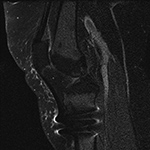

Susceptibility Artifact. (A) Sagittal proton-density-weighted fat-saturated image of the knee shows susceptibility artifact arising from three metallic screws for patellar tendon transfer with obscuration of the patellar tendon insertion and proximal tibial marrow.